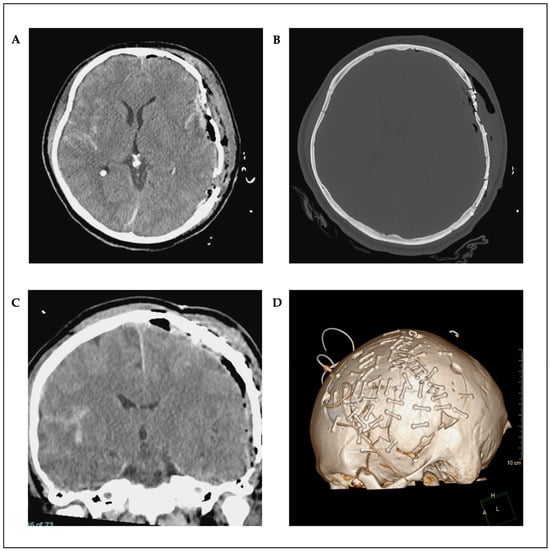

2. Case Presentation

Surgical Technique